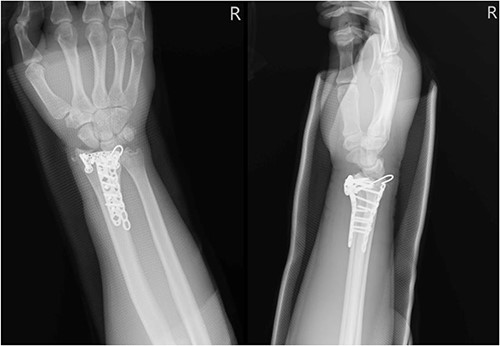

A 61-year-old male who denied any systemic disease, with a past medical history of a left distal radial fracture, which was treated with ORIF with a plate on 29 January 2017. He presented to the plastic surgery Outpatient Department (OPD) in July 2020 with a protruding mass over his left palmar wrist, which had been causing him pain for the past 3 weeks. On examination, poor flexion of the left thumb was noted. Upon suspicion of a ruptured FPL tendon, a sonogram was arranged, which confirmed the diagnosis (Fig. 1). After discussion with the patient, it was decided that he would undergo surgery.

Sonogram of the left wrist showing a ruptured FPL tendon. The arrow points to the discontinuity in the tendon, indicating the site of rupture.